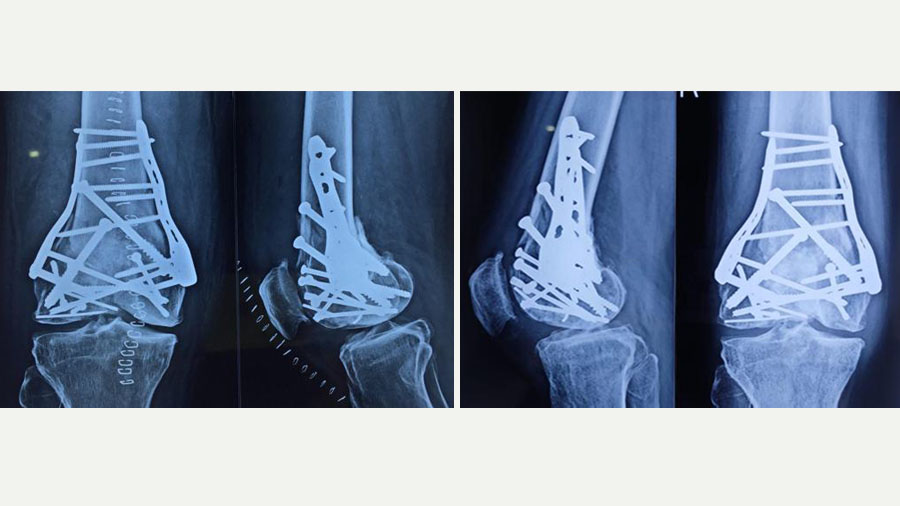

Permanent fixation was then achieved using two plates and multiple screws. Due to the unavailability of a dedicated plate for this particular fracture configuration, we used a shoulder locking plate, which fitted anatomically well for medial and lateral support. This unorthodox but carefully considered decision underscores the importance of improvisation when conventional tools fall short.

We initiated active and assisted active knee motion exercises from the second postoperative day to preserve mobility and prevent stiffness. However, due to the fragility of the fixation and the extensive reconstruction, we delayed weight-bearing for three months. During this time, the patient performed in-bed exercises for joint mobilization.

It wasn’t until the three-month mark that we introduced partial weight-bearing using a walker. Progress was closely monitored both clinically and radiologically. By four and a half months, the patient was walking independently with a cane. At six months post-op, he had resumed driving his motorbike and was able to perform 60-70% of his usual agricultural work.

Now, two years post-injury, the patient is ambulatory without support, actively working on his farm, and satisfied with his recovery. His range of motion is functional, though we have advised him to avoid squatting or sitting cross-legged – common postures in rural India – to minimize joint stress and delay further degeneration.